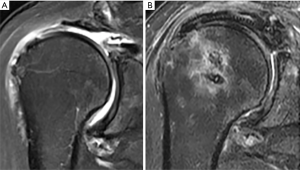

In principle, the rehabilitation of a SCR is similar with the rehabilitation after MIRCT or large IRCT. After the surgery, all patients were placed in a shoulder abduction brace (in 30° to 45° abduction) for 6 weeks and started performing pendulum exercises for 3 weeks. After gaining range of motion after surgery, strengthening exercises for the periscapular muscles and rotator cuff were taught by a dedicated physiotherapist at 3 months after surgery. To date, there has been no studies compared the postoperative protocols after SCR. Recent systematic review showed that most of the current studies will have 3 phases of rehabilitation which consist of sling immobilization phase which ranged from 0 to 6 weeks postoperative, the active range of motion phase which ranged from 3 to 12 weeks postoperative and the strengthening phase which ranged from 6 weeks to 6 months postoperative (52). Previous studies describe that the risk of retear following large size rotator cuff repair is higher when early mobilization (53,54). For this reason, delayed mobilization can be plausibly suggested after SCR rather than early mobilization to decrease graft failure rate. In our institution, a routine shoulder plain radiograph and MRI scans at 3, 6, and 12 months postoperatively were performed in all patients. MRI was preferred over ultrasonography for its accuracy in assessing graft integrity (55) (Figure 7).